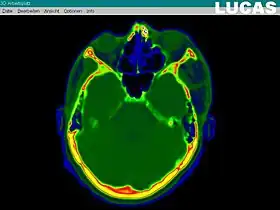

The most important component for CAS is the development of an accurate model of the patient. This can be conducted through a number of medical imaging technologies including CT, MRI, x-rays, ultrasound plus many more. For the generation of this model, the anatomical region to be operated has to be scanned and uploaded into the computer system. It is possible to employ a number of scanning methods, with the datasets combined through data fusion techniques. The final objective is the creation of a 3D dataset that reproduces the exact geometrical situation of the normal and pathological tissues and structures of that region. Of the available scanning methods, the CT is preferred,[1] because MRI data sets are known to have volumetric deformations that may lead to inaccuracies. An example data set can include the collection of data compiled with 180 CT slices, that are 1 mm apart, each having 512 by 512 pixels. The contrasts of the 3D dataset (with its tens of millions of pixels) provide the detail of soft vs hard tissue structures, and thus allow a computer to differentiate, and visually separate for a human, the different tissues and structures. The image data taken from a patient will often include intentional landmark features, in order to be able to later realign the virtual dataset against the actual patient during surgery. See patient registration.

Image analysis involves the manipulation of the patients 3D model to extract relevant information from the data. Using the differing contrast levels of the different tissues within the imagery, as examples, a model can be changed to show just hard structures such as bone, or view the flow of arteries and veins through the brain.